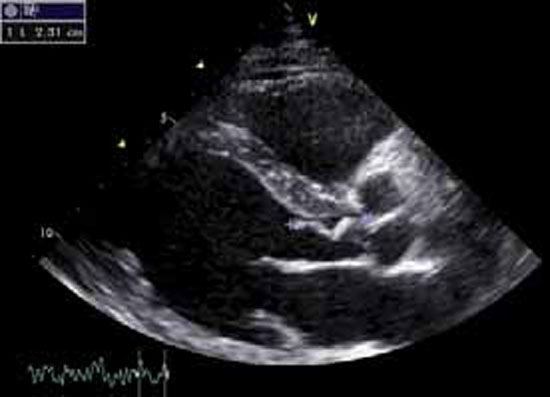

Les dégâts et la présence d’éventuelles complications sont appréciés: capotage ou désinsertion d’une valve, perforation valvulaire (figure 4), rupture de cordage, anévrysme du sinus de Valsalva.

Sur les prothèses valvulaires, abcès péri-annulaires et désinsertion de prothèse (figure 5) sont fréquents.

Figure 5 : Endocardite sur prothèse mitrale mécanique en ETO